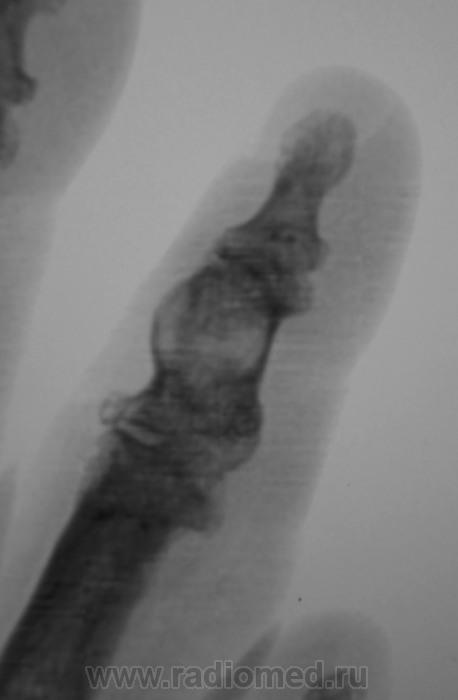

"Пальчик"...

Аневризматическая костная киста. Жалобы есть?

Энхондрома

Туберкулёзный остит средней фаланги 2 пальца.

В дифф.ряд-spina ventosa tuberculosa.

А вот здесь очень близко к костной кисте. Увеличение объема (вздутие), тонкий ободок (стенка) с четкими контурами, содержимое однородное. Даже дифряд строить не хочется.